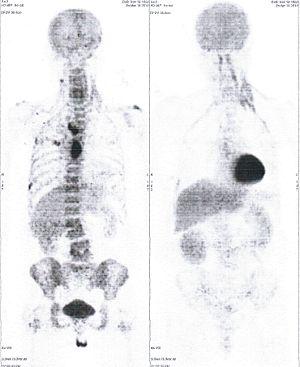

CASE NO: 3 (PROSTATE CANCER)

A middle-aged man with castration resistant prostate cancer, having failed all currently available cancer treatment, was very weak, and getting worse every day. The PET/CT scan showed he had massive bone metastases. After a few treatment, all the bone metastases went into remission. About 6 months later, he is still in remission.

CASE NO: 4 (PROSTATE CANCER)

A middle-aged man with castration resistant prostate cancer and massive bone metastases, failed all currently available cancer treatment, including with the new and expensive drug XTANDI. After a few treatment, most of the bone metastases went into remission, and the remaining ones are less active. Treatment will continue. Cases no: 3 and 4 show that terminal prostate cancer today can be cured with our new cancer treatment.